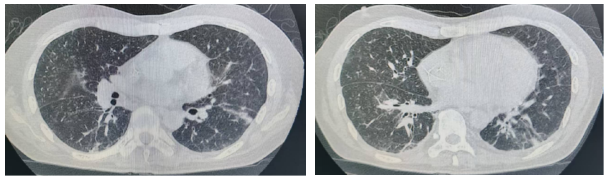

图1. 2024-05-13 胸部HRCT影像